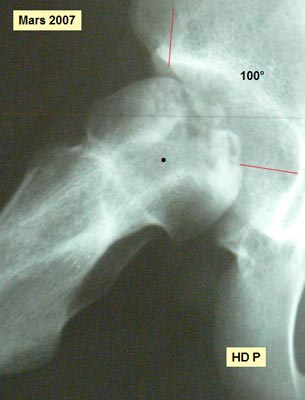

OSTEONECROSE SEVERE de la Hanche Droite Résection de la nécrose intra-céphalique Histoire Clinique Mlle M.N. est née le 23 juillet 1991. A l'âge de 14 ans, apparition d'une boiterie et de douleurs du genou gauche. Une Rx de la HG met en évidence une épiphysiolyse de grade 2. (45°). Un vissage bilatéral est pratiqué fin novembre 2004. Au début de février 2006, la hanche droite devient douloureuse et se bloque. Il s' agit d'une ONA. Aucune étiologie d'ordre médical n'est retrouvée. Le matériel est retiré quelques jours plus tard. Deux thérapeutiques sont évoquées : soit une greffe de moelle osseuse, soit une ostéotomie inter-trochantérienne. L'arthro-scanner de mars 2006 montre l'aplatissement de la tête fémorale, l'enfoncement de la partie portante nécrosée, la déformation en miroir du toit et un épanchement intra-articulaire de stade 3. L'IRM confirme la nécrose de grade III. Après entretiens avec les parents, il est décidé de pratiquer un nettoyage de la zone nécrotique suivi d'un comblement-greffe à l'aide d'un composite formé d'un biomatériau et de moelle osseuse. L'intervention a lieu en mai 2006. La hanche est mise en décharge avec deux CB. La reprise de l'appui est progressive en fonction de la tolérance clinique en respectant la règle de la non-douleur. La marche sans canne est autorisée en mars 2008. Nous verrons les résultats 22 mois après l'intervention.

Que se passe t'il à l'intérieur de l'os ? Clichés comparatifs intermédiaires - A : L'IRMN avant la greffe de biomatériau montre l'étendue de la nécrose sur la hanche de face. - B : L'IRMN postopératoire à 10 mois précise l'étendue de la nécrose dans la tête fémorale « in situ ». - C : Les Rx standards pré et postopératoire à 16 mois précisent l'évolution de la nécrose. - D : Les Rx standards post - opératoire à J + 1 et à 16 mois précisent l'évolution du biomatériau. ETENDUE de la NÉCROSE